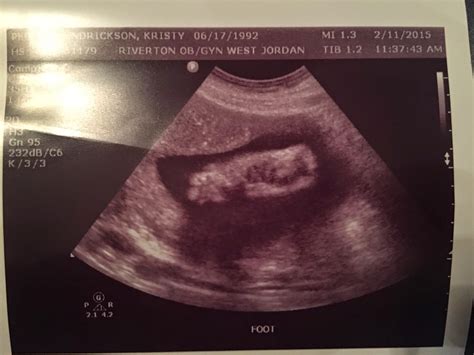

The Normal Amniotic Index (NAI) is a measurement used to quantify the amount of amniotic fluid present in the uterus. It is typically assessed using ultrasound imaging. The index is calculated by dividing the uterus into four quadrants and measuring the deepest vertical pocket of amniotic fluid in each quadrant. The sum of these measurements provides the Normal Amniotic Index.

The Normal Amniotic Index is typically measured during routine ultrasound examinations. The process involves:

• Positioning the mother in a comfortable position, usually lying on her back.

• Applying ultrasound gel to the mother’s abdomen.

• Using an ultrasound transducer to visualize the uterus and measure the deepest vertical pocket of amniotic fluid in each of the four quadrants.

• Summing the measurements to obtain the Normal Amniotic Index.